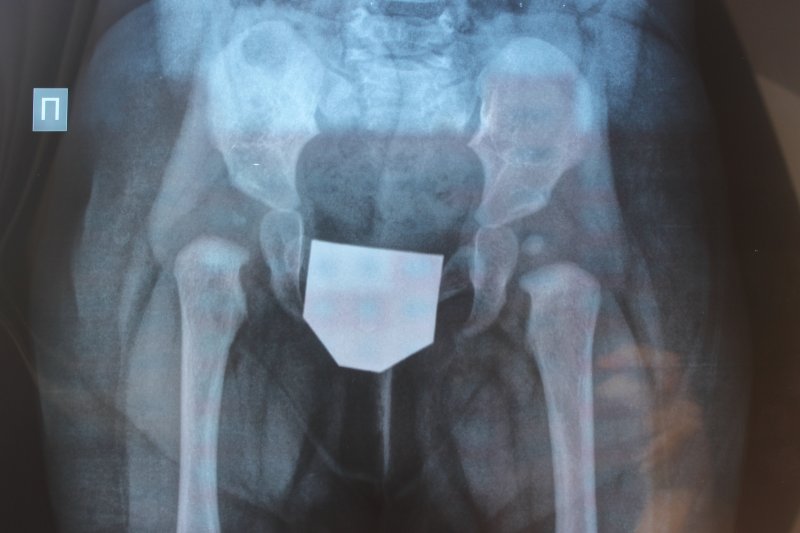

Я так понимаю, Принцессе почти 7 месяцев? :) Я думаю щелчок никак не связан с ношением шины. Чтобы полноценно ответить на ваши вопросы, мне бы хотелось посмотреть на рентгенограмму. Попробуйте сфотографировать ее, и прицепить к письму.

Дмитрий Олегович Сагдеев

и еще вопросик - нет ли на снимке неправильной укладки?

Лесик

Я думаю, щелчок скорее всего был, просто вы не акцентировали на нем внимание. Он происходит при размыкании суставных поверхностей, это признак нестабильности сустава. Посмотрев рентгенограмму, я рекомендовал бы вам вместо перинки Фрейка, шину Виленского. Полностью исключите нагрузку на ноги.